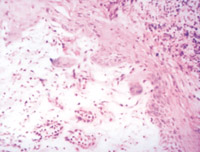

5-2-4 傷后第5天,真皮淺層組織液化性壞死、剝落  HE×100